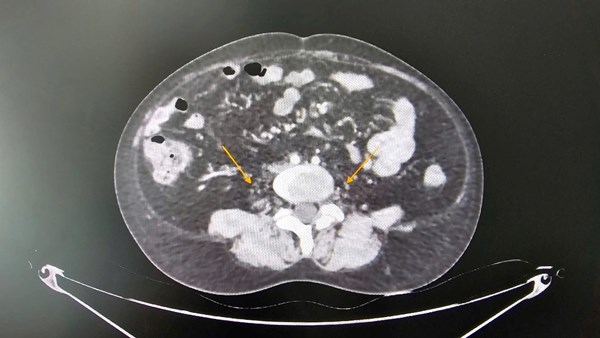

Ca phẫu thuật 7 tiếng đồng hồ cứu bệnh nhân HIV bị biến chứng do tiêm silicon ngực